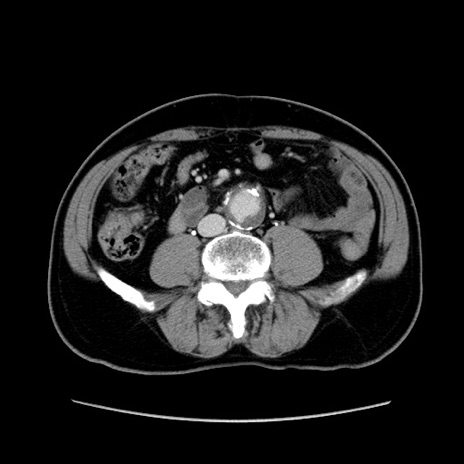

【症例】60歳代 男性

【主訴】右鼠径部膨隆

【現病歴】1年程前より右鼠径部膨隆あり。自己にて還納可能だったため放置していた。3時間前より右鼠径部の脱出を認め、還納困難となり受診。

【既往歴】高血圧

【身体所見】右鼠径部に小児頭大の膨隆あり。弾性硬であり、用手還納は困難。左鼠径部にも膨隆を認める。脱出はなし。